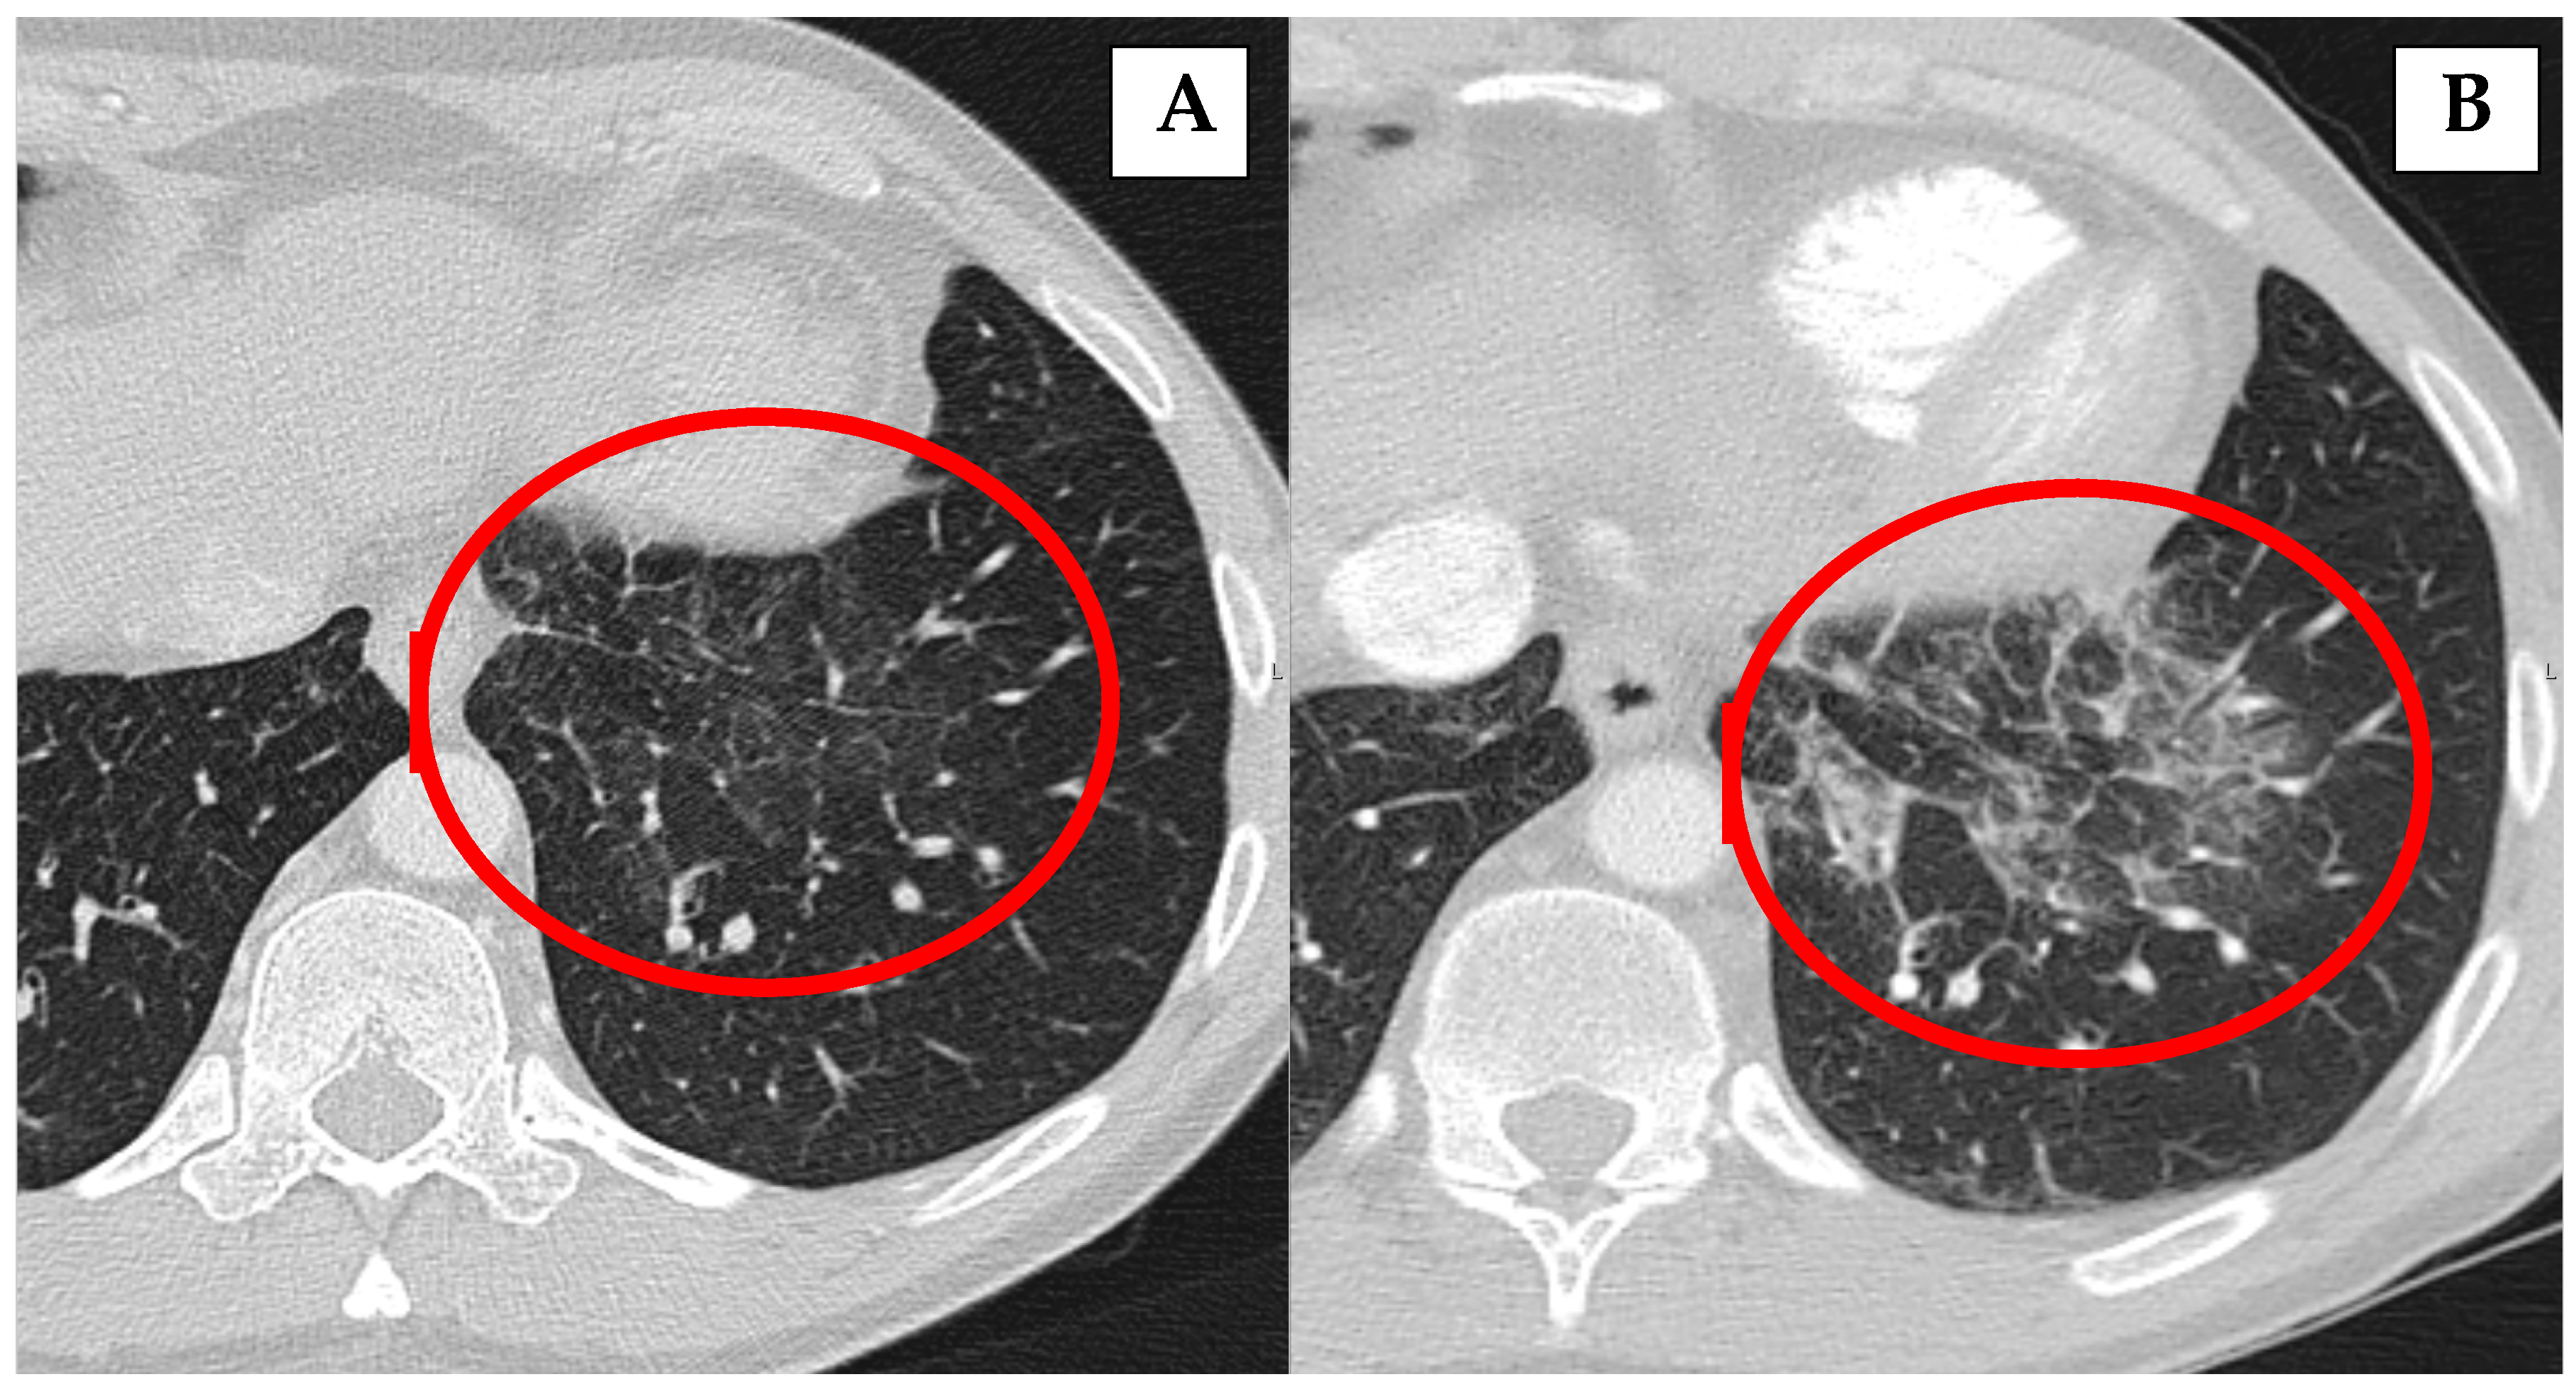

| 1 | female | 53 | Type 1 | 1 year after AIP diagnosis: “ground-glass” appearance; relapse after 12 years of AIP diagnosis with pleura thickening and mediastinal lymph nodes enlargement | No treatment | Former (13 PY) |

| 3 * | male | 66 | Type 1 | 9 months after AIP diagnosis: nodular lesions in lungs | Rituximab and CST 2.5 mg | Never |

| 4 * | female | 65 | Type 1 | 2 months after AIP diagnosis: nodular lesions in lungs | Rituximab | Never |

| 5 * | male | 85 | Type 1 | At the time of AIP diagnosis: non-specific infiltrates in both lung lobes | Previously treated with CST, currently no treatment | Former (10 PY) |

| 6 * | female | 24 | Type 1 | At the time of AIP diagnosis: infiltrates in both lung lobes with pleural effusion | Previously treated with CST, currently no treatment | Never |

| 8 | female | 73 | Type 1 | 5 months after AIP diagnosis: nodular lesions in lungs | Previously treated with CST, currently no treatment | Never |

| 10 | female | 60 | Type 1 | 3 years after AIP diagnosis: “ground-glass” appearance and pleura thickening | Previously treated with CST, currently no treatment | Former (10 PY) |

| 11 | male | 69 | Type 1 | 5 years after AIP diagnosis: nodular lesions in lungs | Previously treated with CST, currently no treatment | Never |